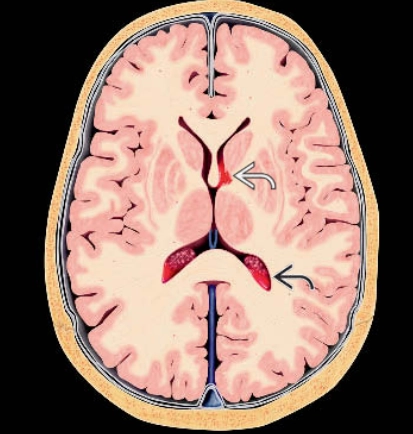

• Xuất huyết trong nhu mô não tự phát không do chấn thương (Spontaneous Nontraumatic Intracranial Hemorrhage - pICH)

• Xuất huyết não do tăng huyết áp (Hypertensive Intracerebral Hemorrhage - HICH)